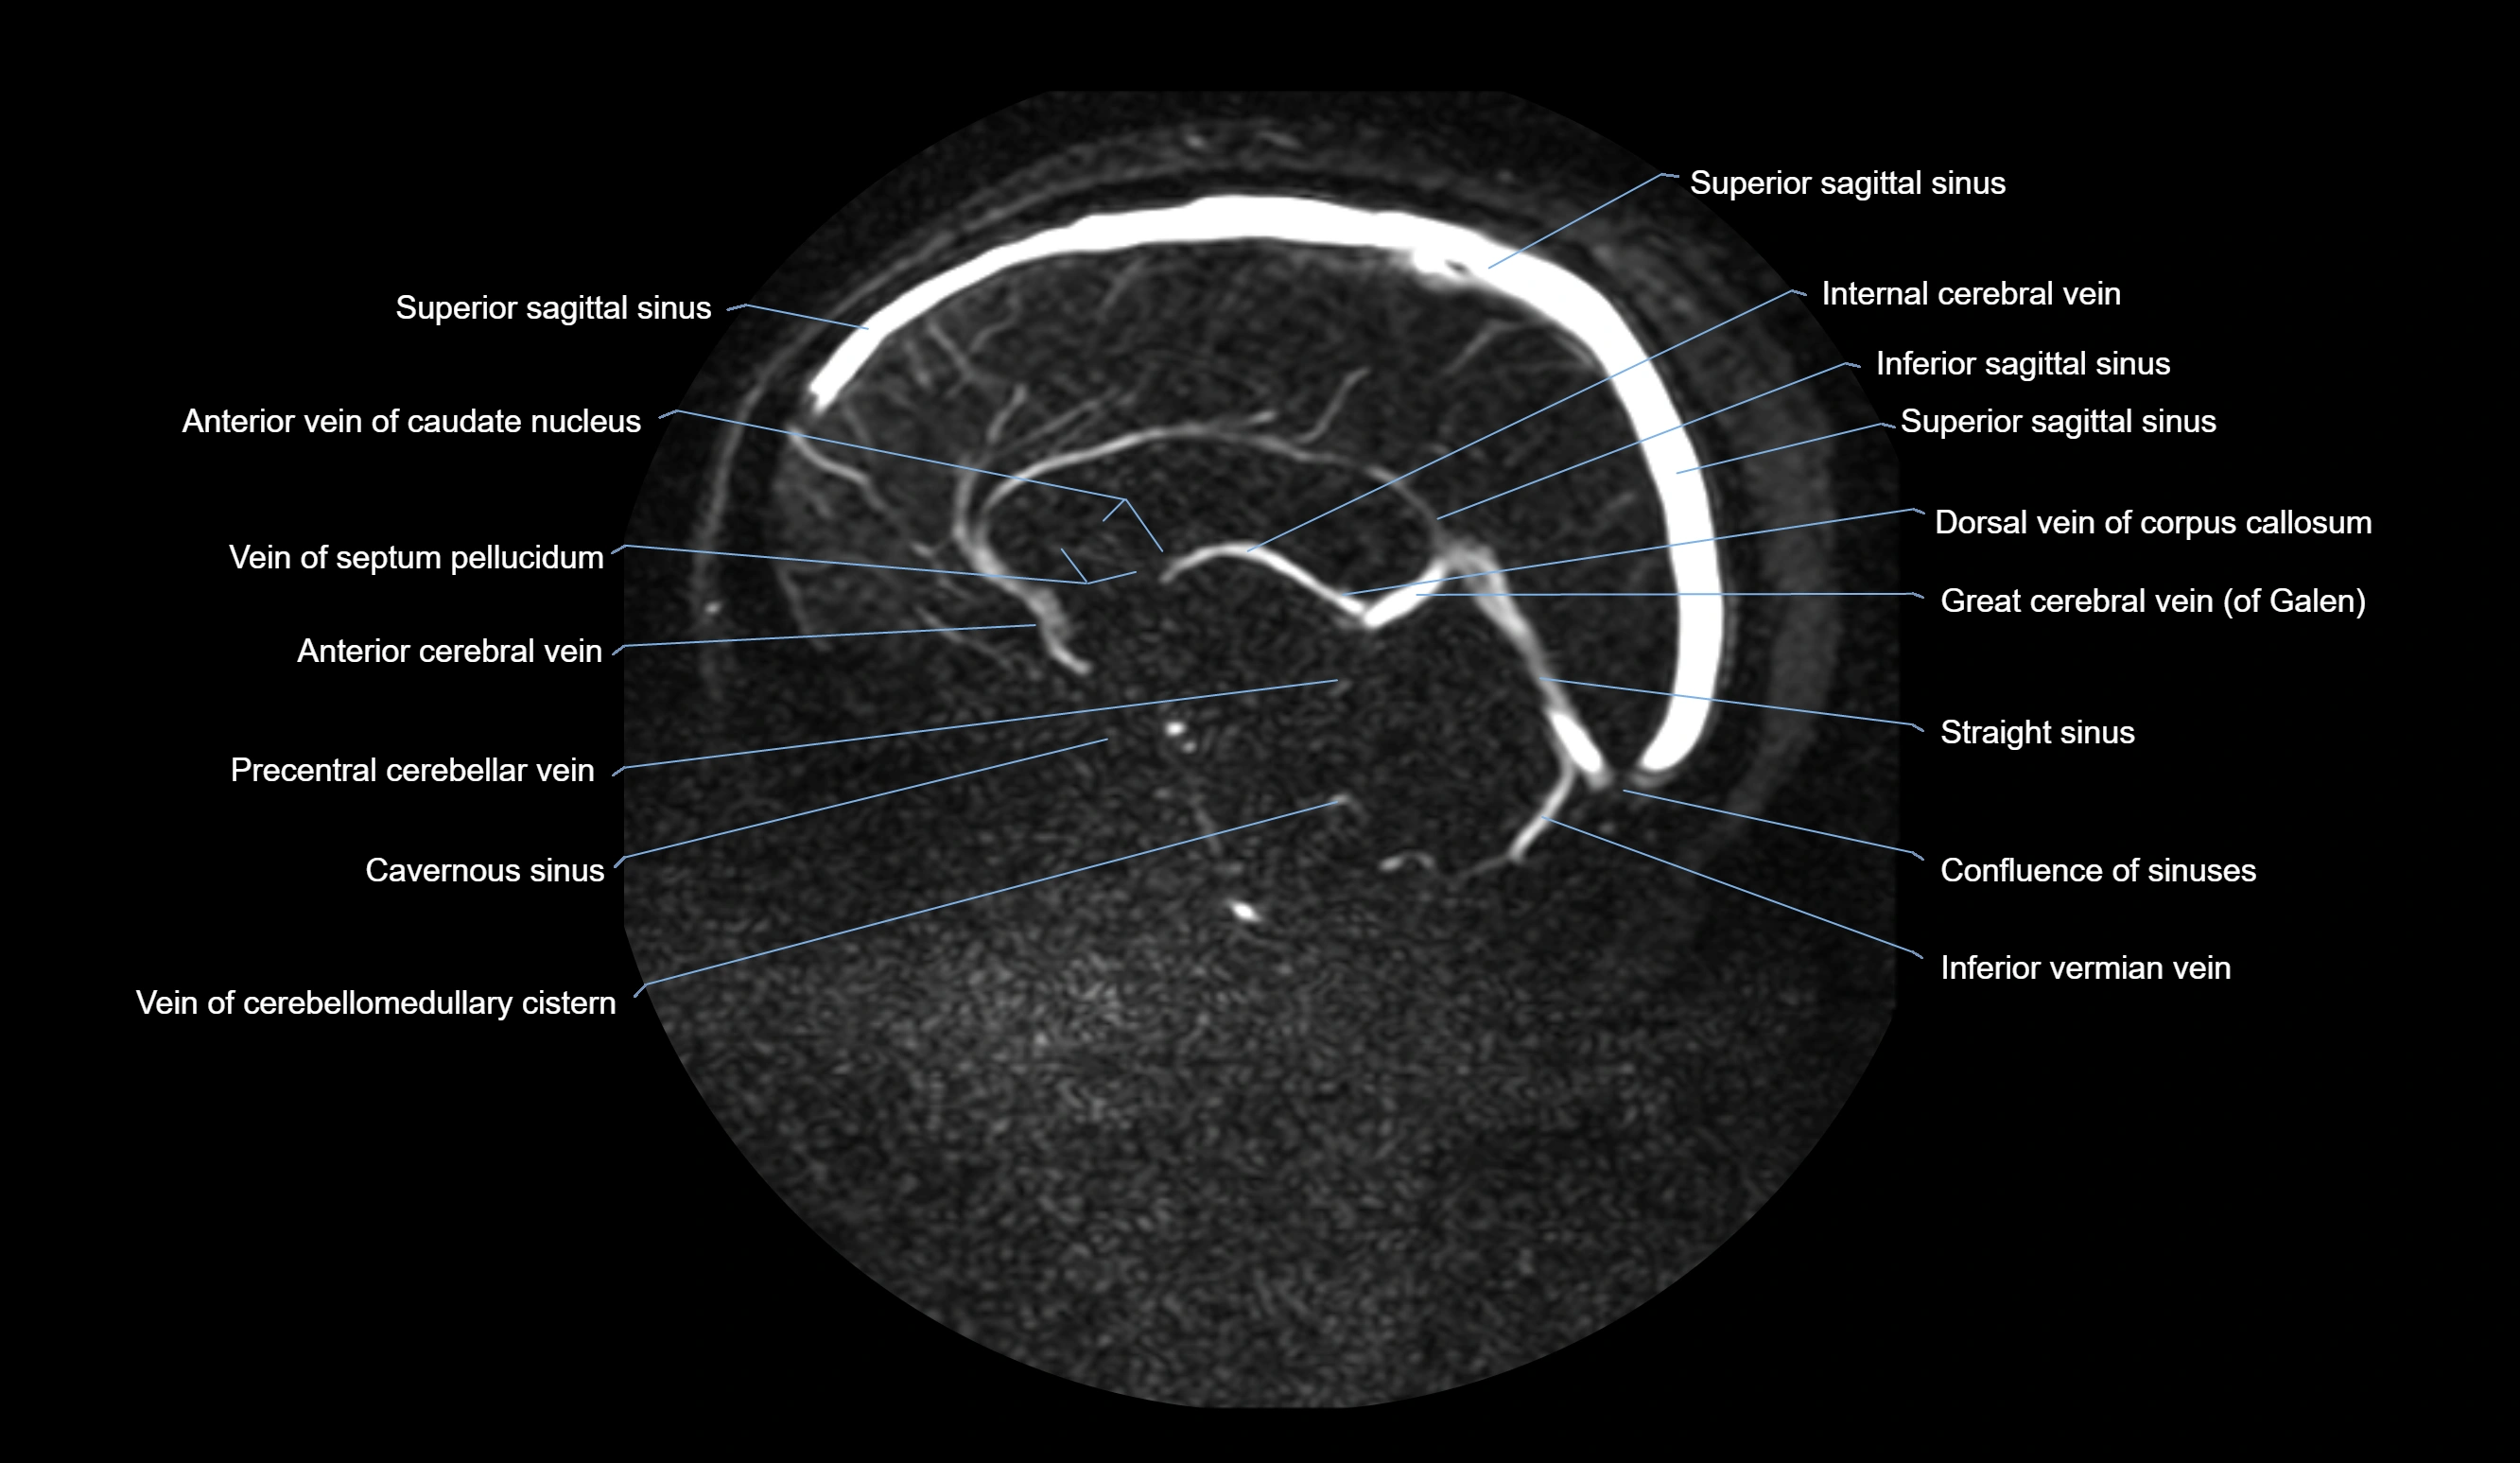

MRI images

image